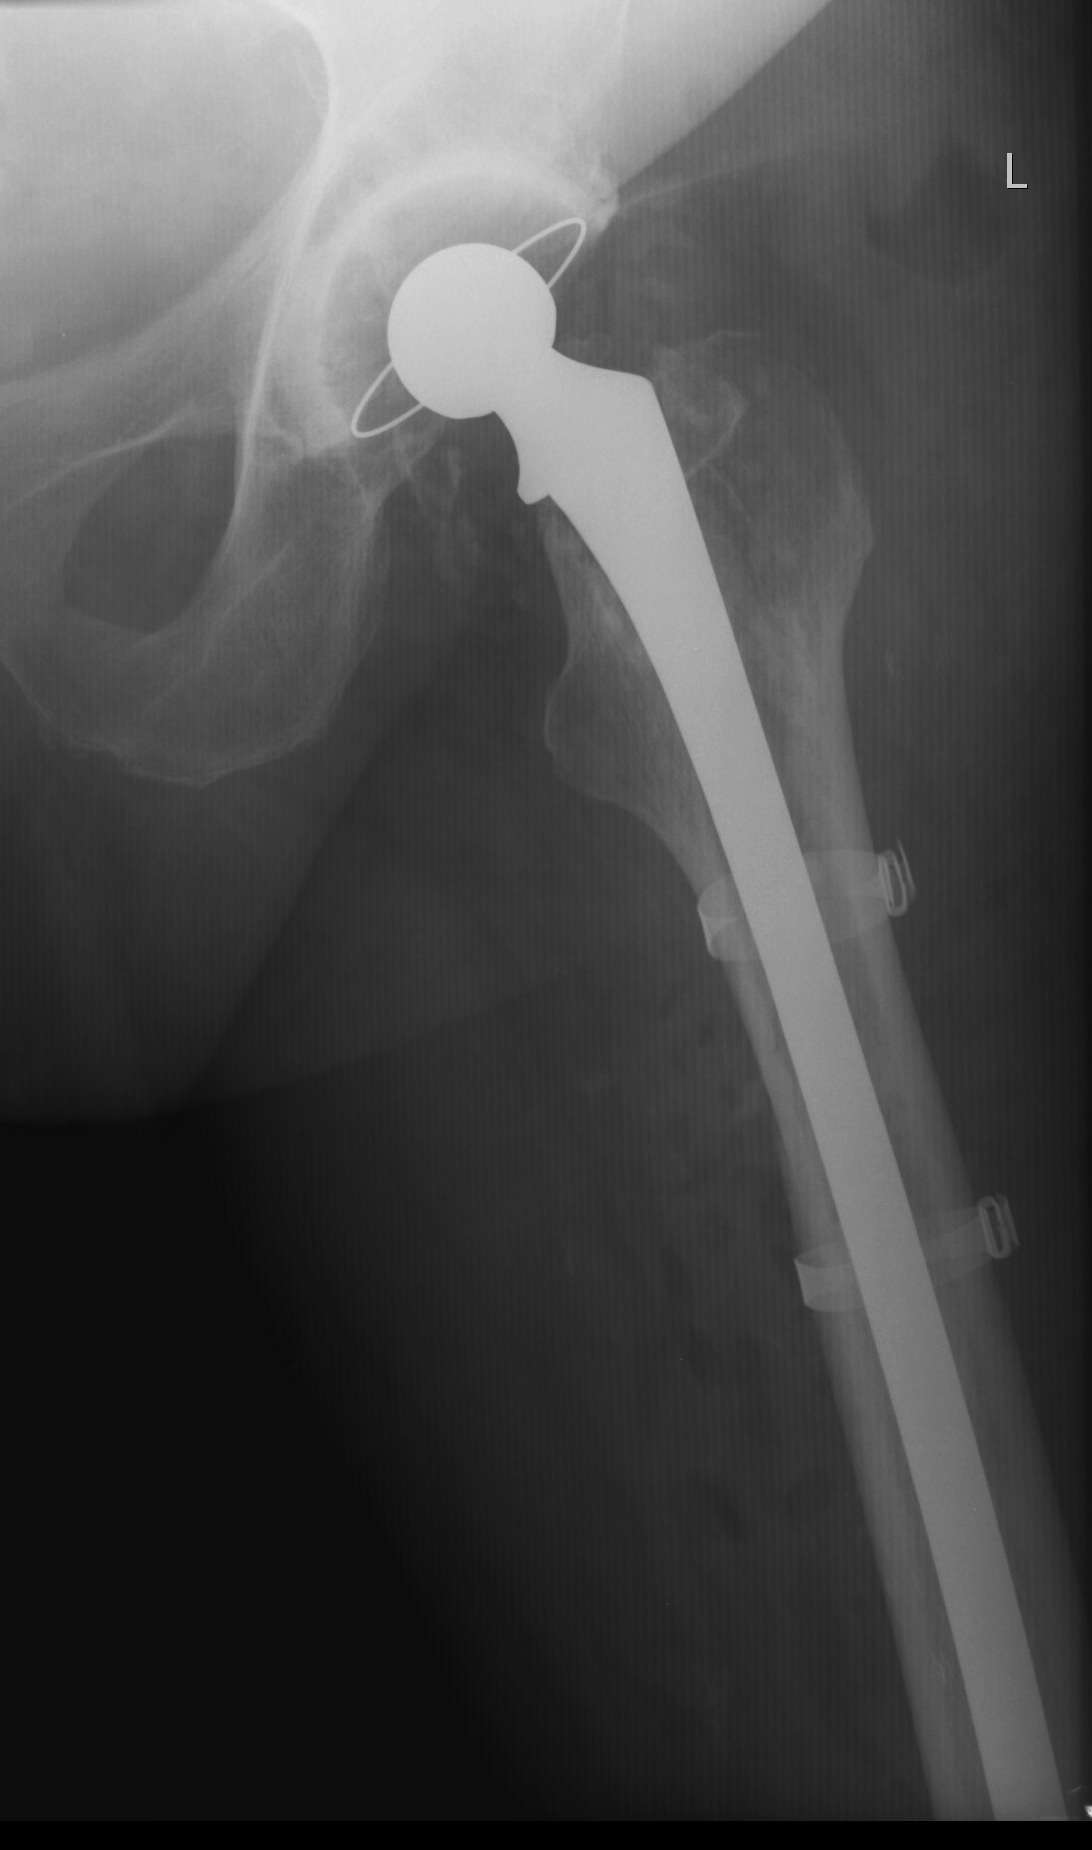

Long stem uncemented revision

Revision uncemented arthroplasty with Zimmer cable plate

Long stem uncemented revision with cortical strut allograft

Long stem uncemented revision with plate + cortical struts